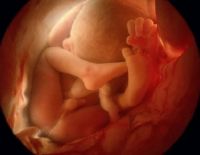

Các mốc siêu âm 4D quan trọng mà mẹ không nên bỏ lỡ

Các mốc siêu âm 4D là một trong những điều rất quan trọng. Mẹ nên chú ý để đi khám thai và siêu âm đúng lịch. Mỗi một mốc siêu âm 4D sẽ giúp mẹ biết thêm rất nhiều thông tin và chỉ số sức...

Siêu âm 4D nhiều có tốt không? – Điều mẹ cực kỳ nên biết!

Siêu âm 4D nhiều có tốt không? Là vấn đề mà nhiều chị em quan tâm nhất khi đang trong thời gian thai kỳ. Họ sợ rằng sóng siêu âm 4D gây ảnh hưởng không nhỏ tới sự phát triển của đứa bé trong bụng....

Thai 20 tuần tuổi siêu âm 4D được không thưa bác sĩ?

Thai 20 tuần tuổi có siêu âm 4D được không? là câu hỏi được nhiều mẹ quan tâm nhất khi chuẩn bị khám thai. 4D là một trong những công nghệ siêu âm thai nhi tốt hàng đầu hiện nay, giúp mẹ có thể hiện...